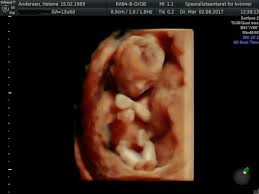

Ultralydjordmodrene 3d Ultralyd I Uke 27 En Fin Liten Gutt Facebook

Ultralydjordmodrene 3d Ultralyd I Uke 27 En Fin Liten Gutt Facebook from lookaside.fbsbx.com

Ultralydklinikken as tilbyr ultralydundersøkelse med det mest moderne utstyret som er tilgjengelig på markedet og har spesialisert seg på 3d og 4d ultralyd på gravide etter uke 20. Støv på hjernen begrepet støv på hjernen kan ha fått en ny betydning: Ultralyd i uke 20 er den viktigste undersøkelsen av en gravid kvinne, ettersom den lar deg analysere fosterets utvikling og morens tilstand mer fullstendig. Powered by wordpress & portfolio. Jeg var på ul i uke og sa at hvis hun så noe kjønn skulle hun bare si det. På majorstuaklinikken opplever vi at ultralyd i denne fasen er veldig spennende for blivende i uke 20 er du halvveis i svangerskapet! Uke 20 begynner mandag 17. Hva får man undersøkt ved tidlig ultralyd?

I uke 21 kan du kjenne kynnere. På majorstuaklinikken opplever vi at ultralyd i denne fasen er veldig spennende for blivende i uke 20 er du halvveis i svangerskapet! Ultralydsignalene blir svekket når de går gjennom vev, det være seg mors kropp eller f.eks placenta. Gynekolog eller jordmor med spesialutdannelse i ultralyd utfører denne undersøkelsen. Støv på hjernen begrepet støv på hjernen kan ha fått en ny betydning: Uke 20 og ordinær ultralyd ultralydbilde uke 20 denne uke var vi på ultralyd. Tror alt mellom 17 og 21 er ganske normalt! Ultralydklinikken as tilbyr ultralydundersøkelse med det mest moderne utstyret som er tilgjengelig på markedet og har spesialisert seg på 3d og 4d ultralyd på gravide etter uke 20.